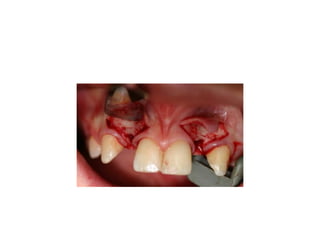

pre-op

palatal inflammation is noted from

retainer

implants are placed w/in restorative

Management of missing upp incisor